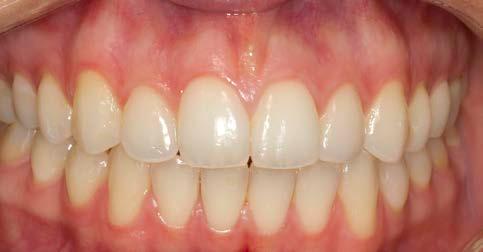

Discussion

At the end of the procedures, the restoration was precisely seated at equigingival level of the margins, it appeared to be morphologically integrated in the dental arch, with correct contact points and with a good chromatic match with the adjacent elements (Figs. 21-24). Upon X-ray examination, it was possible to see that the subgingival margins were also integrated, without any step or any plaque-retaining area that could be a problem for the home dental hygiene (Fig. 25). The patient didn’t refer pain anymore and was completely satisfied with the prosthetic rehabilitation, that she found perfectly integrated at both functional and chromatic levels. She also found the colour of the prosthesis was better than her natural teeth.